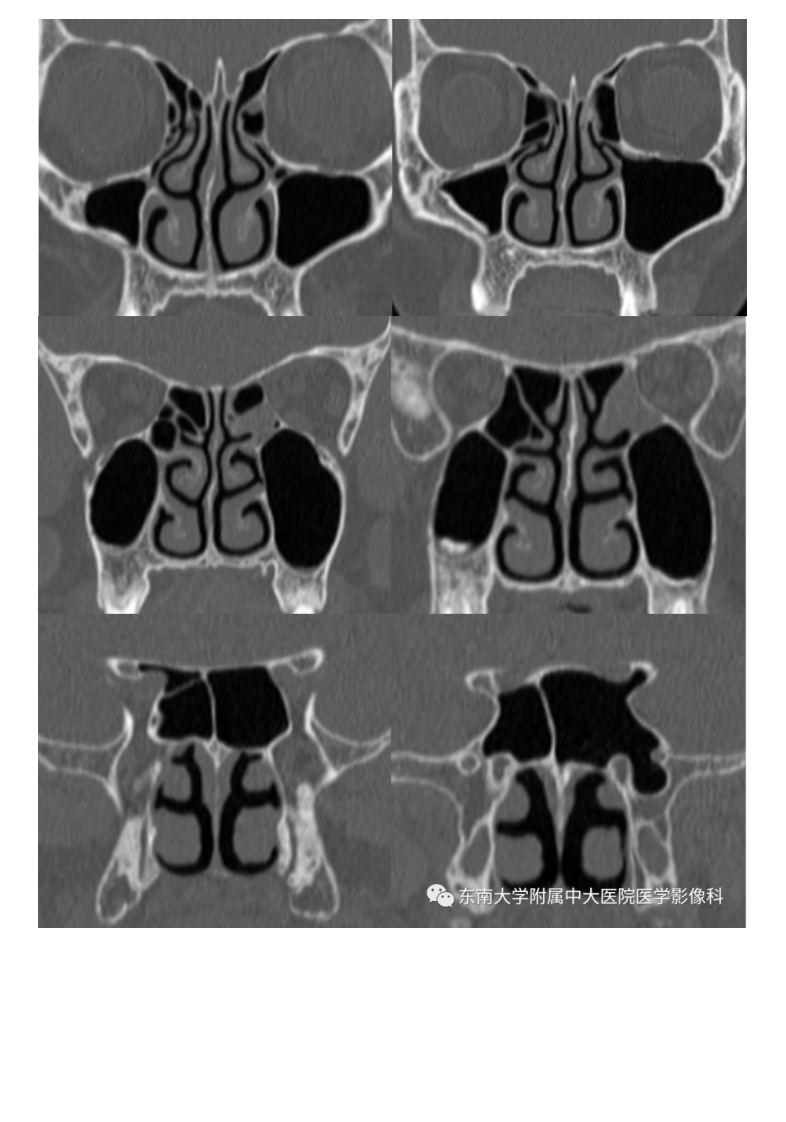

20200707_2【晨读结果公布】2020.07.06头颈部疾病——副鼻窦解剖变异.pdf